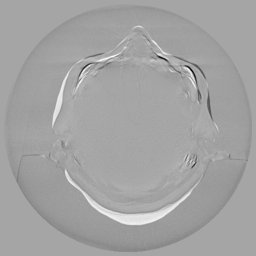

III-C Uncertainty analysis

Classical diffusion models reconstruct images by progressively denoising from an initial Gaussian noise image, a process that inherently introduces uncertainty due to random noise initialization. In contrast, I2SB directly learns a diffusion bridge between two sample distributions, effectively bypassing the need for random noise sampling and thereby reducing reconstruction variability.

To assess the uncertainty of our method, we performed multiple reconstructions using different random seeds. As shown in Fig. 3, the ground truth and representative sampled images are presented in Fig. 3(a) and (b–d), respectively. The mean reconstruction and pixel-wise standard deviation across runs are displayed in Fig. 3(e) and (f). Only minimal differences are observed between reconstructions, indicating that I2SB produces highly consistent results. These findings confirm that, compared with classical diffusion models, I2SB substantially reduces uncertainty across repeated reconstructions.